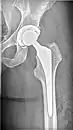

![]() | |

| X-ray of hip with femoral head osteonecrosis | |

ANFH can only be diagnosed by MRI of the hip and X-rays of the hip specifically in the anteroposterior and frog-leg lateral poses.[2] Along with these scans an additional bone scan needs to be done which allows doctors to see the activities of bone cells in a body. Once the images that the physician want are obtained, they are then measured through two systematic reviews.